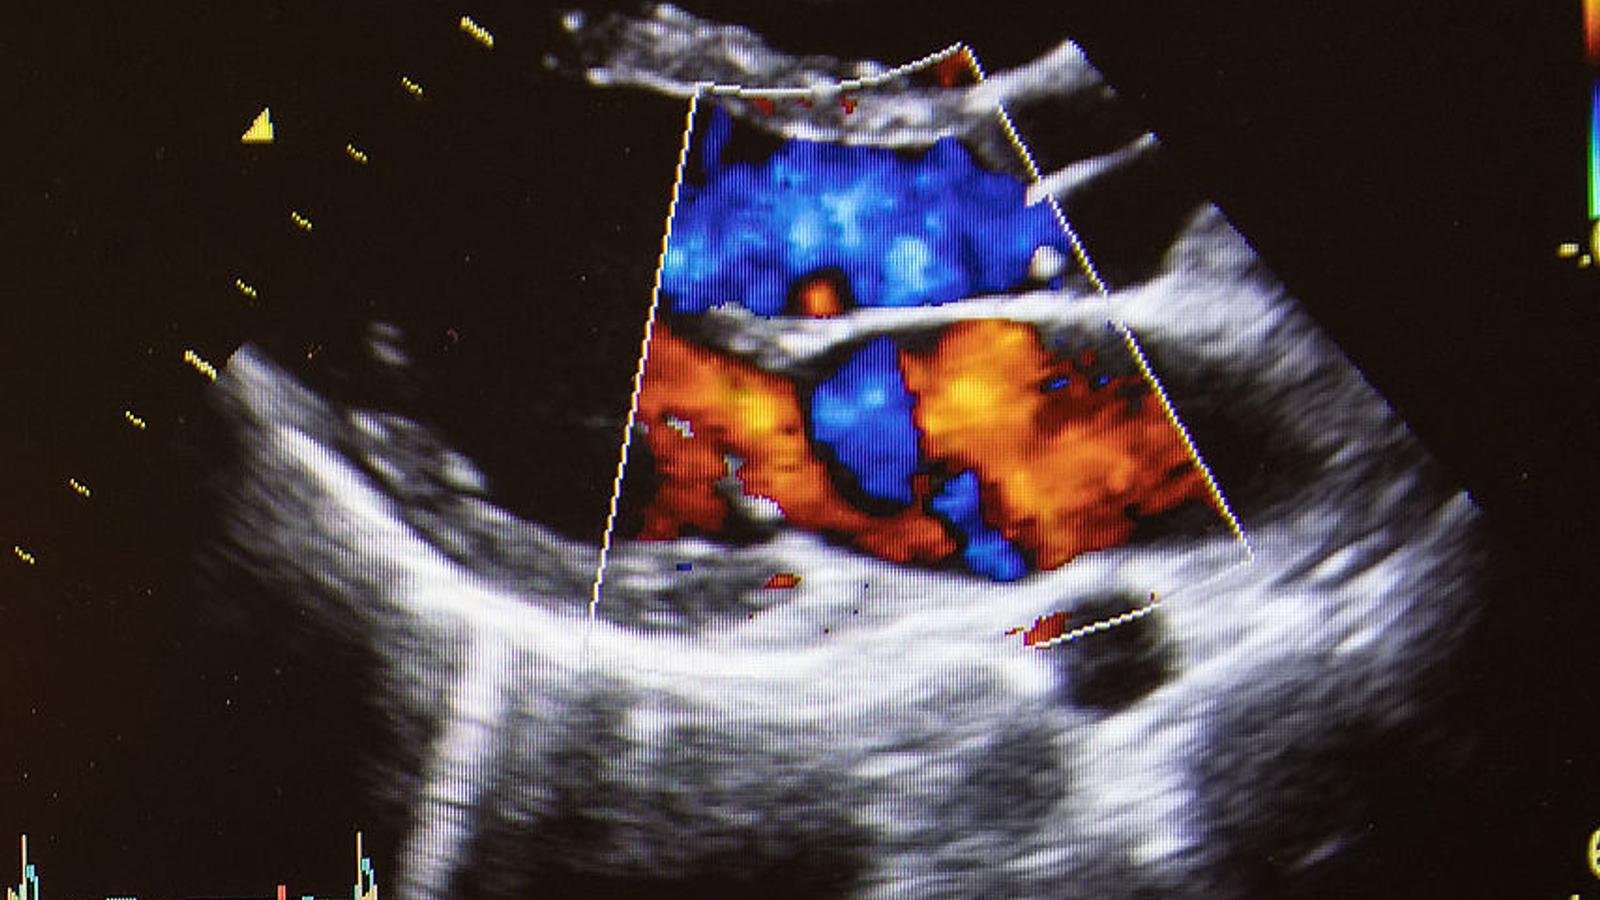

Bei der Elastographie wird das Gewebe in unterschiedlichen Farben dargestellt. So kann gesundes von krankem Gewebe unterschieden werden.

Krankhafte Gewebsveränderungen sind tastbar und das macht sich die Elastographie zu Nutze. Sie ist eine Weiterentwicklung der herkömmlichen Methode der Sonographie bzw. der Magnetresonanztomographie. Unterschiede der Elastizität des untersuchten Gewebes werden in Farbe dargestellt und ermöglichen so Rückschlüsse auf krankhafte Veränderungen von Gewebe. Durch eine Elastographie kann beurteilt werden, ob ein Tumor bös- oder gutartig ist. Krankhaftes Gewebe wie z.B. Tumoren haben eine andere Festigkeit als gesundes Gewebe und genau das wird in einem Elastogramm abgebildet.

Liefert eine normale Ultraschalluntersuchung zu wenige Informationen, kann eine Ultraschall-Elastographie weitere Erkenntnisse bringen. Bei den meisten Ultraschall-Elastographietechniken übt der Untersucher mit einem speziellen Ultraschallkopf leichten Druck auf das betreffende Organ aus. Für den Patienten ist dieser Druck nicht wahrnehmbar. Anders als ein herkömmliches Ultraschallbild wird eine Elastogramm in Farbe dargestellt. So können zusätzliche Informationen über die Elastizität einer Gewebeveränderung gewonnen werden.